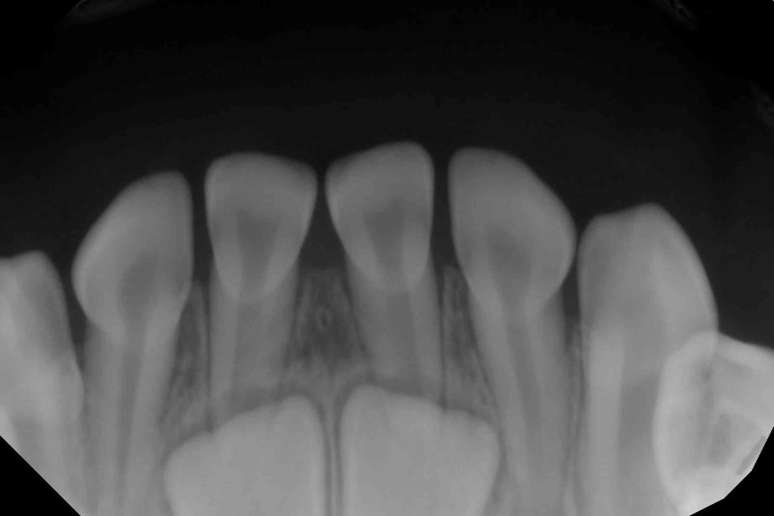

A maioria das pessoas nasce sem nenhum dente visível na boca, embora os dentes de leite comecem a se desenvolver antes mesmo do nascimento. Os dentes de leite geralmente começam a aparecer na gengiva quando você tem entre 6 e 8 meses de idade. Às vezes, quando os dentistas fazem raios-X para verificar se há cáries ou outros problemas, eles podem ver os dentes permanentes crescendo dentro da gengiva.

Imagem em preto e branco mostra uma fileira de dentes pequenos com raízes – abaixo deles, há dois dentes brancos maiores

Foto: The Conversation

Radiografia da boca de uma criança mostra dois dentes permanentes crescendo na mandíbula, abaixo dos dentes de leite visíveis. David Avenetti